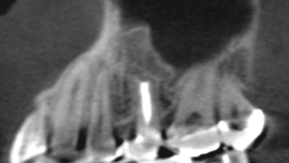

約1年半後のレントゲンでは、炎症によって失われていた骨が再生している様子が確認できました。

歯を抜かずに保存できたことで、患者さまには大変喜んでいただけました。

After